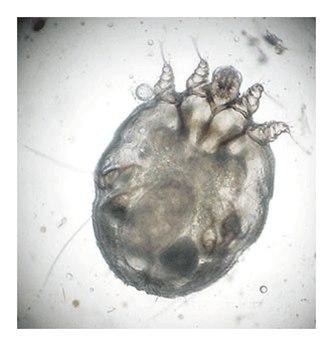

Bilde av skabbmiddSkabbutslett kan likne en lang rekke hudsykdommer. For å kunne stille diagnosen, vil legen foreta en samlet vurdering bestående av både symptomer, sykehistorien, utslettet og ved behov tilleggsundersøkelser. Det finnes forskjellige måter å påvise skabbgangene. Noen ganger er de synlige med det blotte øye, noen ganger ved hjelp av optiske hjelpemidler. Det kan også brukes blekk eller en spesiell type lys for å oppdage skabbganger. Sikker diagnose stilles dersom legen klarer å isolere skabbmidd eller egg fra huden til pasienten og kan bekrefte funnet ved undersøkelse i mikroskop. I praksis kan dette være vanskelig. I slike situasjoner kan den typiske sykehistorien, utslettet og eventuelt funn på skabbganger være tilstrekkelig for å stille diagnosen med stor grad av sikkerhet.

Bilde av skabb hos baby.Årsaken til skabb er smitte med en midd som har navnet Sarcoptes scabei var. hominis. Denne midden er 0,3-0,4 mm lang og kan derfor så vidt ses med det blotte øye. Hunnmidden graver ganger og legger egg i gangene. Hun lever i cirka én måned, befruktes flere ganger og legger 2-3 egg om dagen. Etter at eggene er klekt, gjennomgår larvene to nymfestadier før de blir voksne midd.